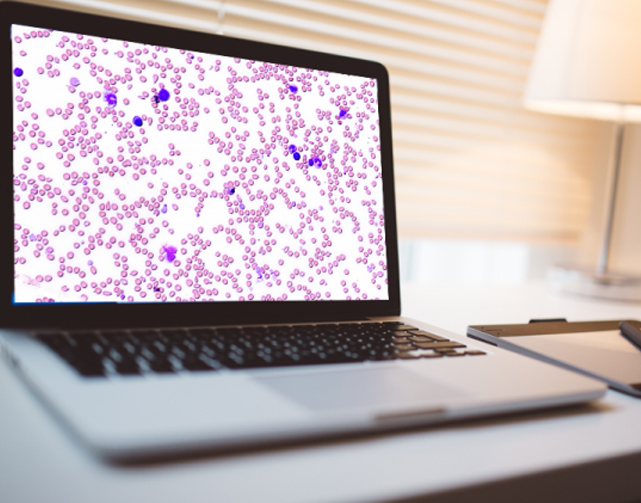

3DHISTECH Ltd. (the name is derived from „Three-dimensional Histological Technologies”) is a leading company, developing high-performance hardware and software products for digital pathology since 1996.As the first European manufacturer, 3DHISTECH is one of the market leaders in the world with more than 1500 sold systems. Being one of the pioneers in this field, 3DHISTECH develops and manufactures high speed digital slide scanners that create high quality brightfield and ...

Sales of 3DHSITECH procducts used in the field of China digital pathology nearly 200 home users, in addition to the diversity of product combination scheme, also has the high quality pre-sale and after-sale service demonstration.